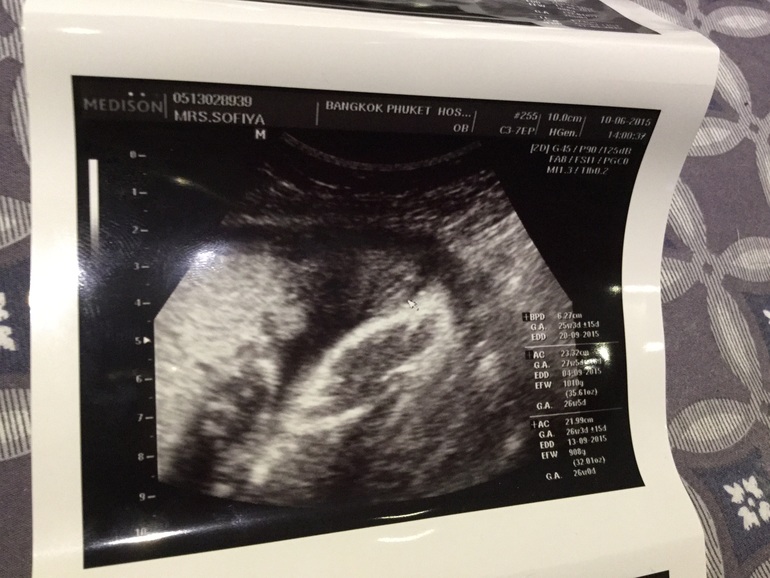

Хлои в Здоровье будущей мамы 10 лет Гляньте девочки кто у нас 😉 Вопросы про УЗИ, обследования и анализы: что, где, как, когда? Девочка или может Мальчик? Девочка 84.8% Мальчик 15.2% Голосовать 92 голоса Посмотрите еще 20 записей на эту тему Отменить Ответить Алена Я НИЧЕГО ВООБЩЕ НЕ ВИЖУ))))) какие вы все молодцы)) 11.06.2015 Ответить Катеринка Пирожочек девушкин)))) у нас такой же был))) 10.06.2015 Ответить chu_do А не подскажете гдеееее? 12.06.2015 Ответить Катеринка В верхней правой части фотографии. Как фасолинка 12.06.2015 Ответить Ирина Конечно девочка! Видно хорошо валик такой)) поздравляю! 10.06.2015 Ответить Надежда Девочка тут, 💯 процентов ! Поздравляю!! ! 10.06.2015 Ответить Элла Девочка:) 10.06.2015 Ответить Мечты сбываются Мне кажеться доченька у вас) 10.06.2015 Ответить Жаклин Девочка! 10.06.2015 Ответить Татьяна А узист -то что сказал? 10.06.2015 Ответить Хлои Говорит вроде девочка . Но не уверен 😉 10.06.2015 Ответить Татьяна Мне что-то совсем не понятно куда смотреть) 10.06.2015 Ответить Хлои Стрелочка прям туда от мышки указывает 10.06.2015 Ответить скриннинг Предлежание хориона на 14 неделе и оргазм... Чаты Беременных Выберите чат: Январята-2026 Февралята-2026 Мартята-2026 Апрелята-2026 Майчата-2026 Июнята-2026 Июлята-2026 Августята-2026